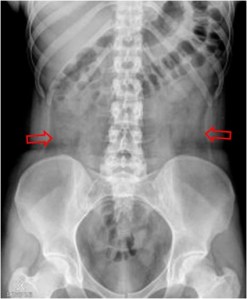

Radiografía de abdomen normal que muestra las líneas grasas de los flancos (flechas).

SIGNO DE LAS OREJAS DE PERRO

En un paciente que presente líquido libre en la cavidad peritoneal, al adoptar la posición de decúbito supino, ésta desciende por efecto de la gravedad hacia las porciones más bajas de la pelvis, acumulándose en las reflexiones pélvicas del peritoneo. Al llenarse los recesos pélvicos laterales a ambos lados de la vejiga urinaria, se forma una imagen densa simétrica que recuerda las orejas de un perro.

Imagen coronal de TC en otro paciente con ascitis rellenando los recesos pélvicos (flechas) que justifican la imagen de la radiografía.